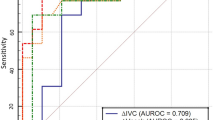

A sample of 58 cases produces a two-sided 95% confidence interval with a width of 0.3 when the sample area under the curve (AUC) in receiver operating characteristic (ROC) analysis is 0.5 (Krzanowski & Hand, 2009).

Our statistical analysis of the collected data revealed that the suggested cut off value regarding baseline IVCCI to predict responder cases was 0.32 with a sensitivity of 72.41%, a specificity of 82.76%, and an AUC of 82.9% (Figs. 1 and 2).